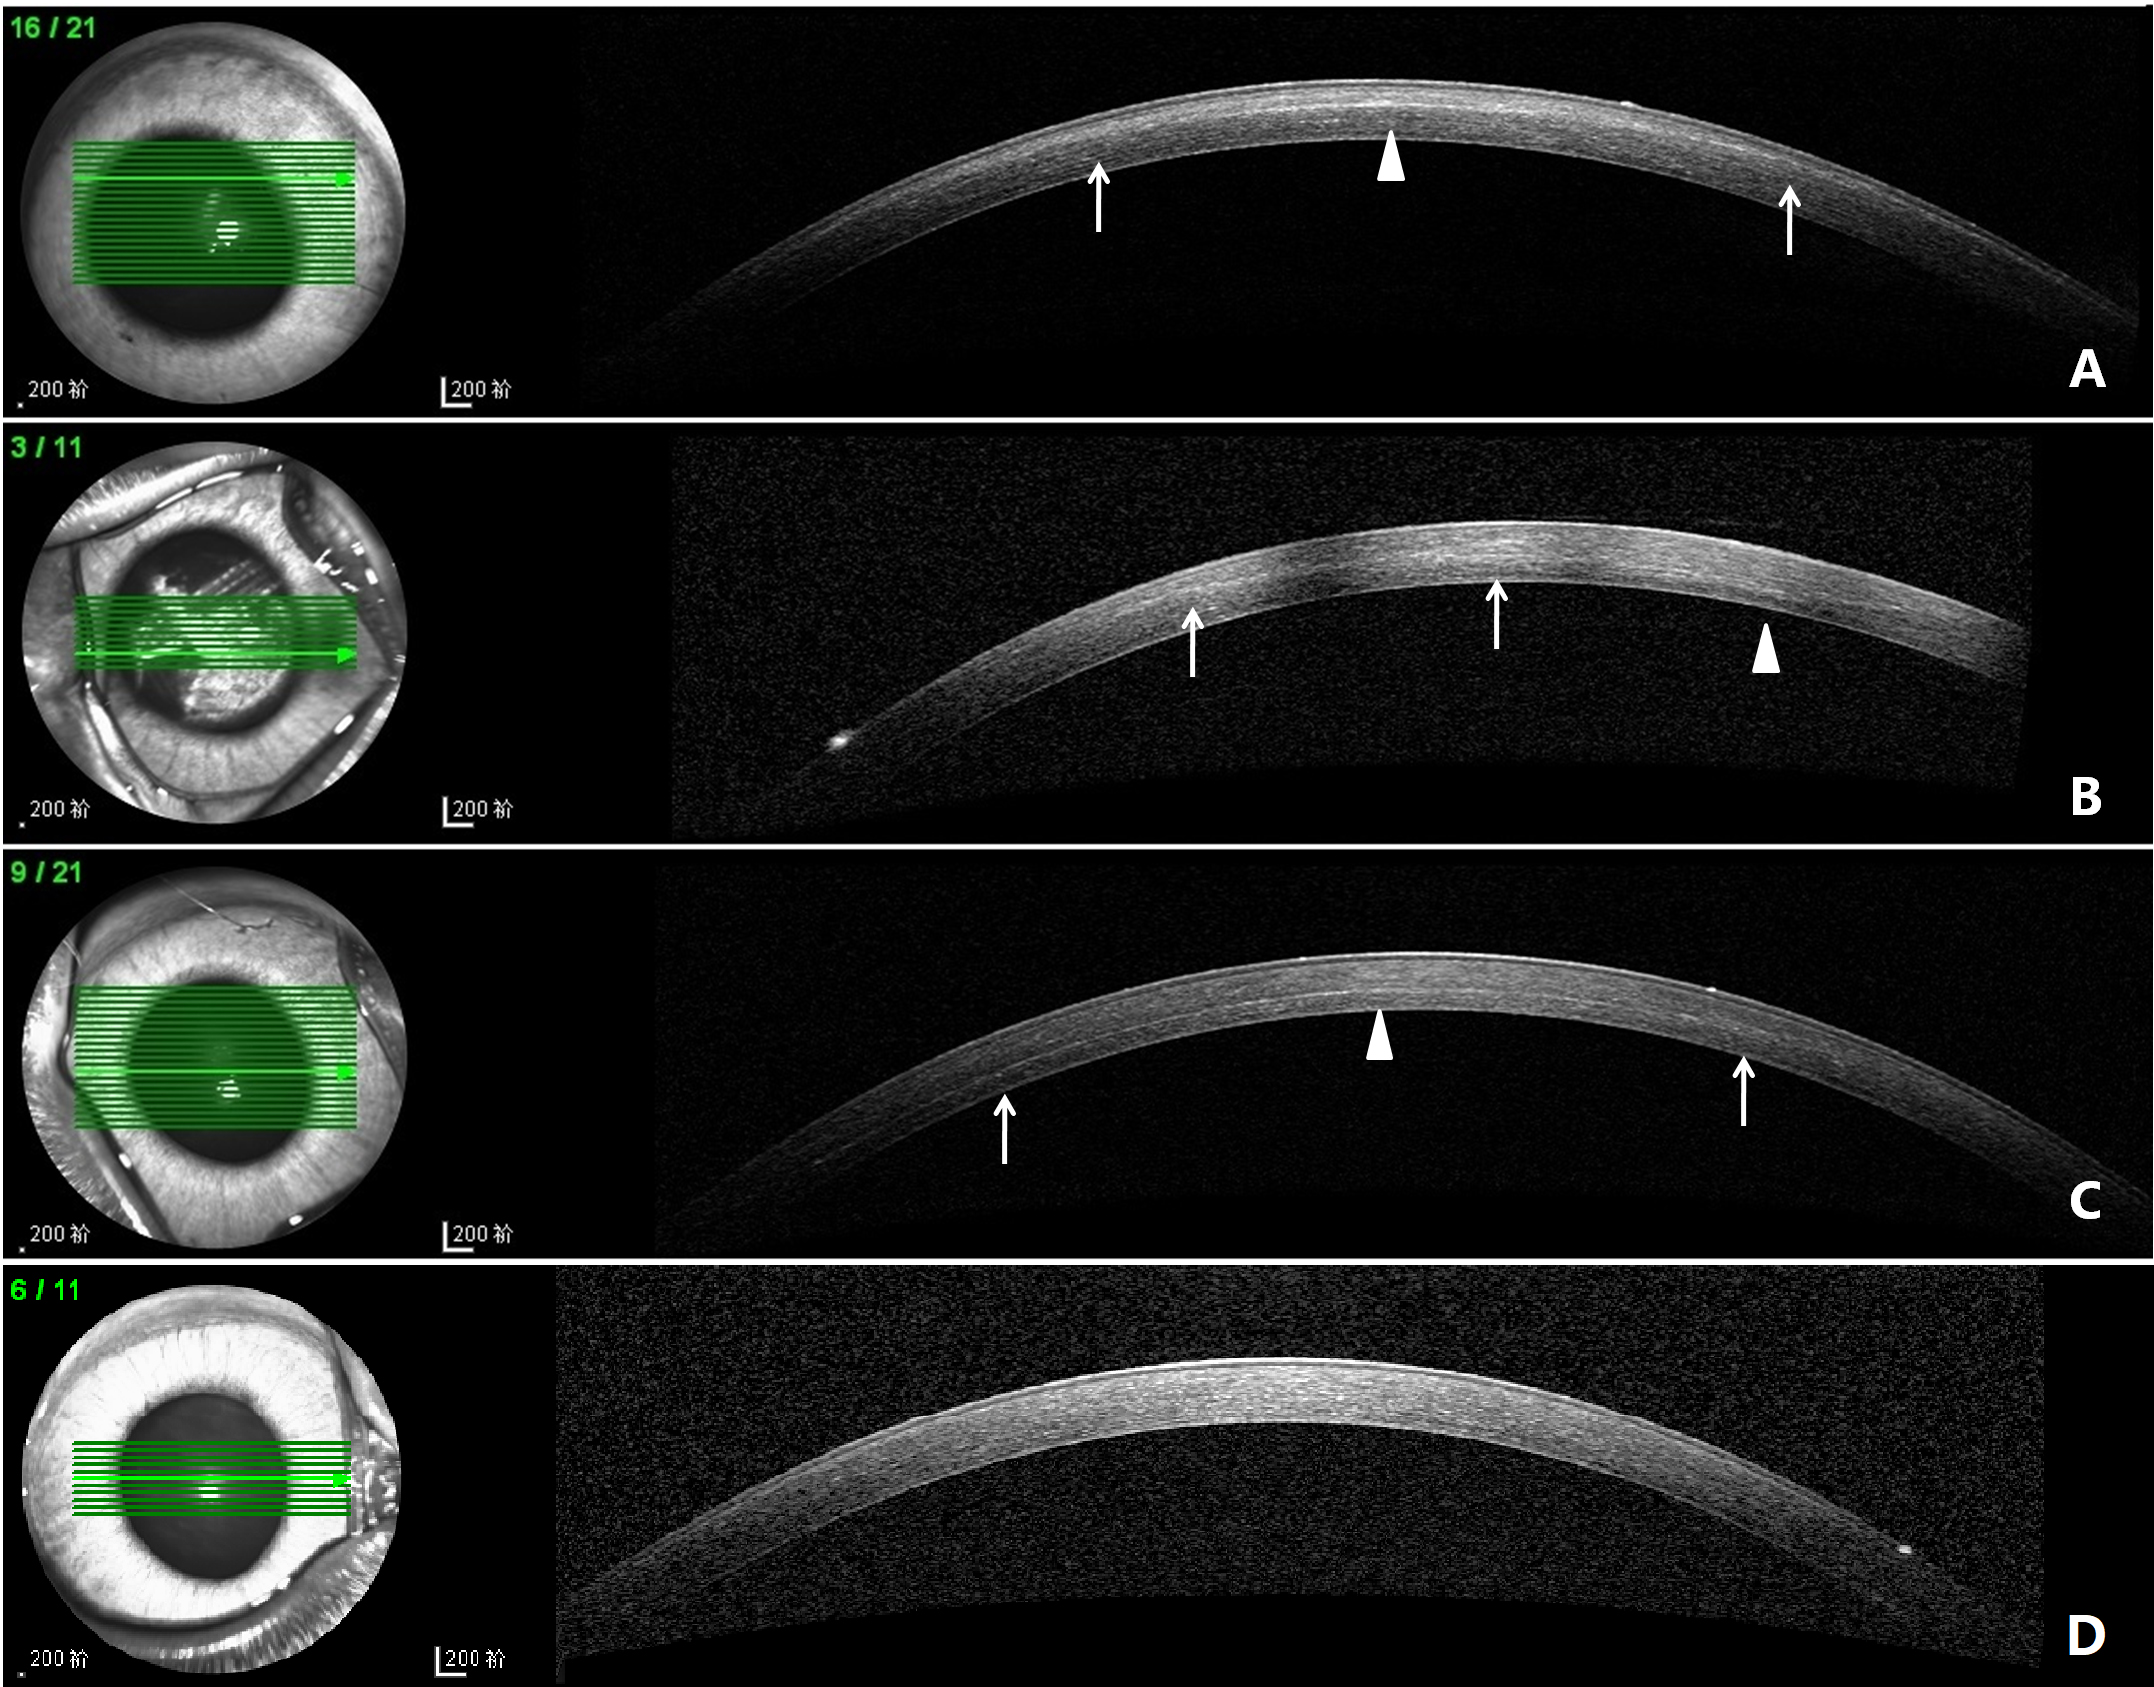

Figure 1. ASOCT images of each group on day 14. A: DL in 0.20% G-CXL group, located in the anterior stroma(arrows). The deepest position was on the superior edge of pupil

(arrowhead). B: DL in 0.25% G-CXL group, located in anterior-mid stroma (arrows). The deepest position was on the nasal edge of pupil. C: DL in UVA-CXL group (arrows). The deepest position was in the cornea center (arrowheads). D: The control group, no DL was

noticed.